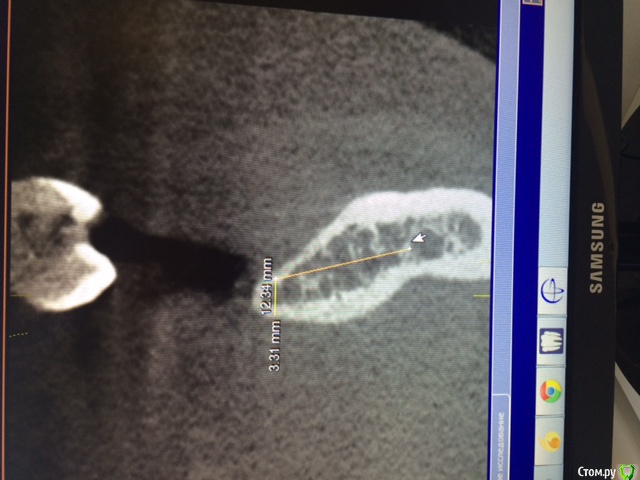

Аслан Опубликовано 24 января, 2015 Поделиться Опубликовано 24 января, 2015 Для начала лучше правильно заливать фотки. Не всем удобно вертеть монитор компа.Ситуация банальная. Их обсуждалось много уже. Нкр (апатос в перемешку с ауто, имплантация. Хотите - одномоментно, хотите раздельно. 1 Ссылка на комментарий